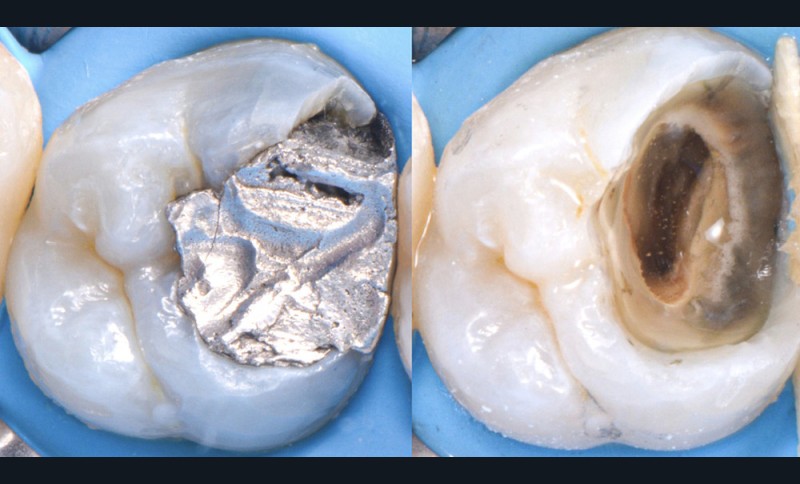

Une cavité d’accès trop petite [2] optimiserait le pronostic biomécanique (préservation dentaire maximale) mais pourrait compromettre le pronostic endodontique : mauvaise lecture de l’anatomie, instrumentation partielle, non ergonomique et avec risque de fracture, défaut de nettoyage des parois canalaires [3], irrigation inadéquate, difficulté d’obturation canalaire, voire d’obturation coronaire. Ce sera le cas des cavités d’accès « Ninja » [4] ou ultraconservatrice (fig. 1), des cavités d’accès « Truss » [5] (fig. 2), des cavités d’accès dites « opportunistes » [6] (fig. 3).

Une cavité d’accès trop large optimiserait le pronostic endodontique mais compromettrait le pronostic biomécanique. C’est le cas de la cavité d’accès traditionnelle, qui a longtemps été « au service » du praticien réalisant le traitement canalaire (dentist-centered dentistry ou dentisterie centrée sur le praticien). Les étapes d’instrumentation, d’irrigation et d’obturation étaient ainsi facilitées grâce à des accès visuel et instrumental exagérés, aux dépens de structures dentaires saines (fig. 4).